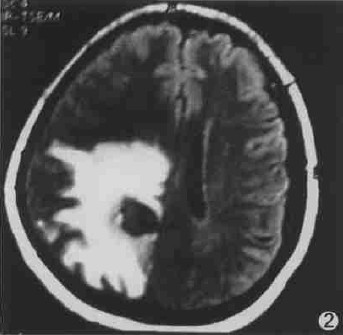

图2 右侧顶叶脑结核瘤内以长T1长T2信号为主的混杂信号,瘤周水肿较重。

2.3 脑结核瘤的MRI影像学特征 ①成熟期19例。其中,干酪性实性中心结核瘤发现28个病灶,周围见轻度水肿带,T1WI呈低或等信号,T2WI呈等或高信号,增强呈环状或花环状强化,强化环壁厚度0.5~1.5cm;干酪性液性中心结核瘤发现50个病灶,周围无或有轻度水肿带,T1WI瘤壁呈等或略低信号,瘤体内呈混杂信号,T2WI瘤壁呈等或略高信号,瘤体内呈混杂信号,增强呈环状强化,壁欠光滑且厚薄不均匀,厚度约0.5~1.0cm。+

②未成熟期4例,共34个病灶,病灶周围见3.0~8.0cm的水肿带,其中12个达8.0cm ,T1WI呈等或略低信号,T2WI呈高信号,增强后呈均匀结节状强化。